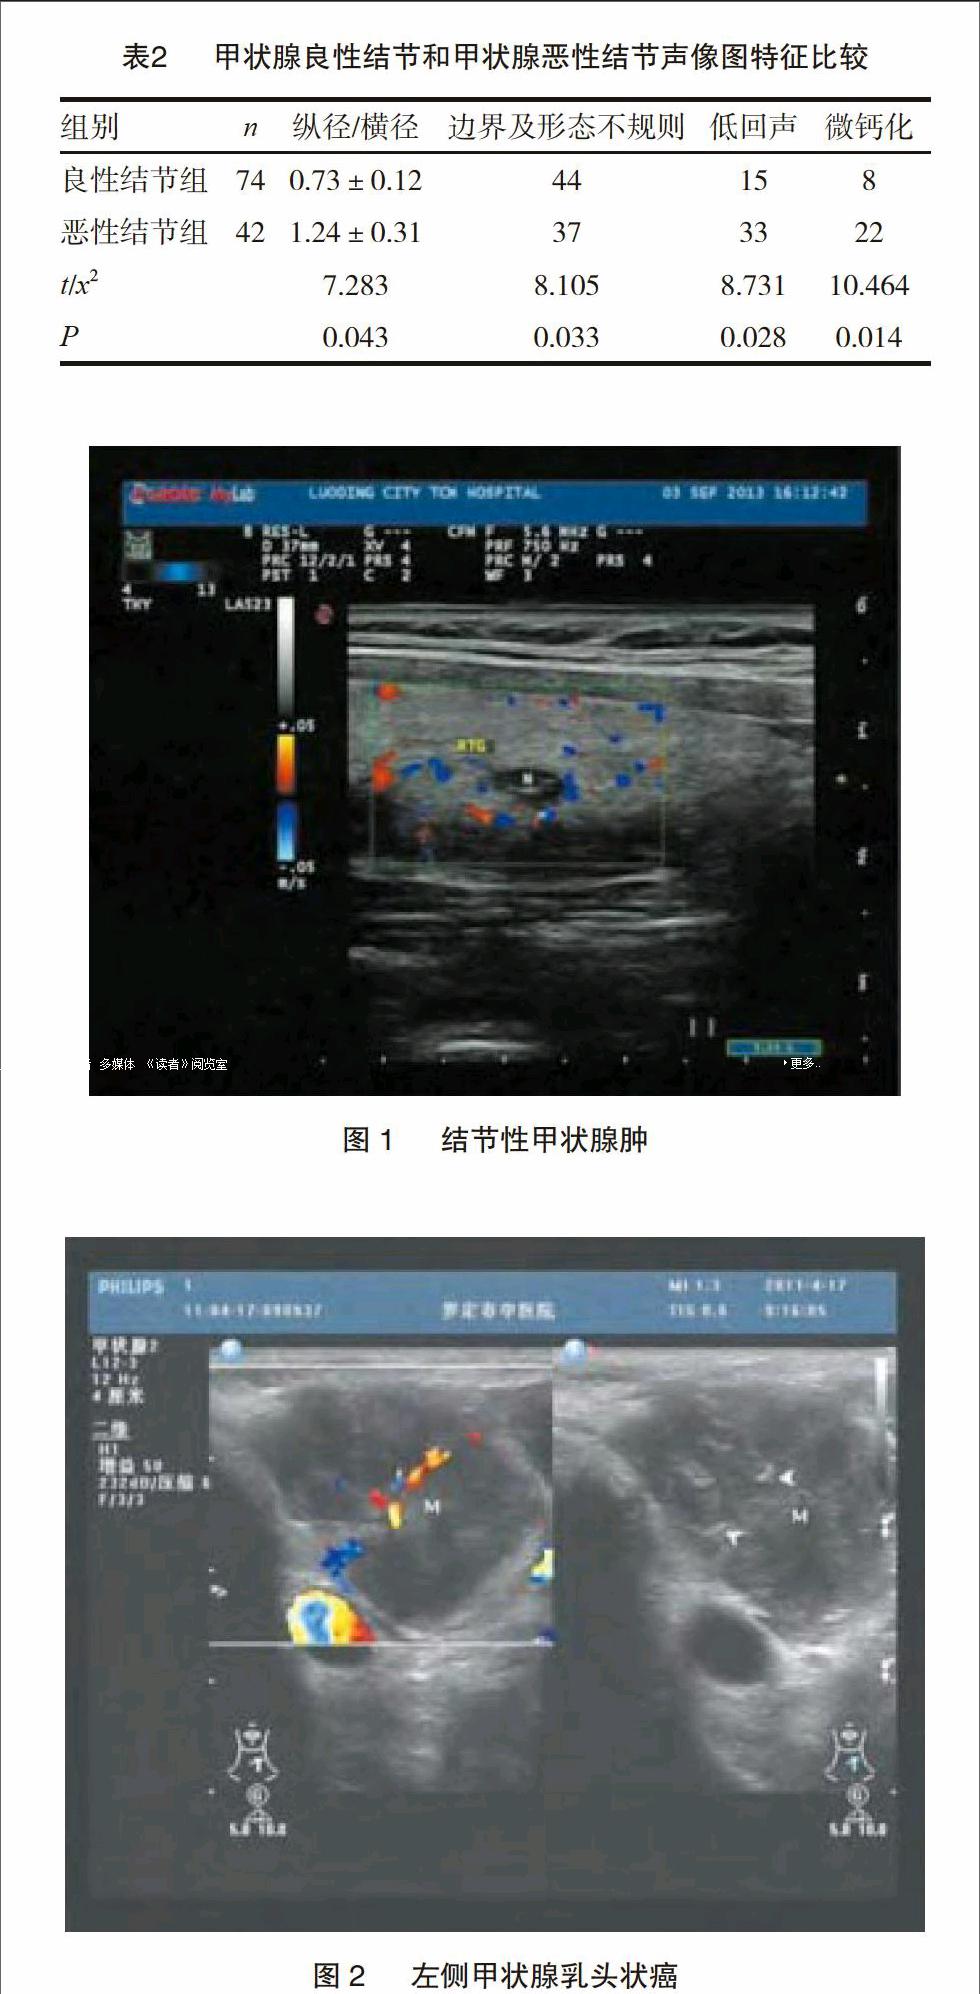

甲状腺结节在人群中发病率较高,但不是所有甲状腺结节都需要处理。一般认为,恶性的需要处理,良性的较大的需要处理,而良性的较小的完全可以不用动它。手术前,判断良恶性主要有彩超和穿刺两种办法。

超声检查本身是个主观性检查,跟超声医师关系非常大,不同医师做出来的结果可能很不相同,有经验的超声医师判断良恶性的准确率可达80%以上,但不能依靠超声来“确诊”。甲状腺结节的良恶性判断很大程度上依赖超声,这成为很多情况下的重要矛盾。要提高判断的准确率,一是可以穿刺活检,但价格较高、检查有创伤,且准确率仍不能达到百分之百;二是到大医院找专科复查彩超,但一般需要预约排队。

您的甲状腺结节边界清,形态规则,所以良性可能性大。